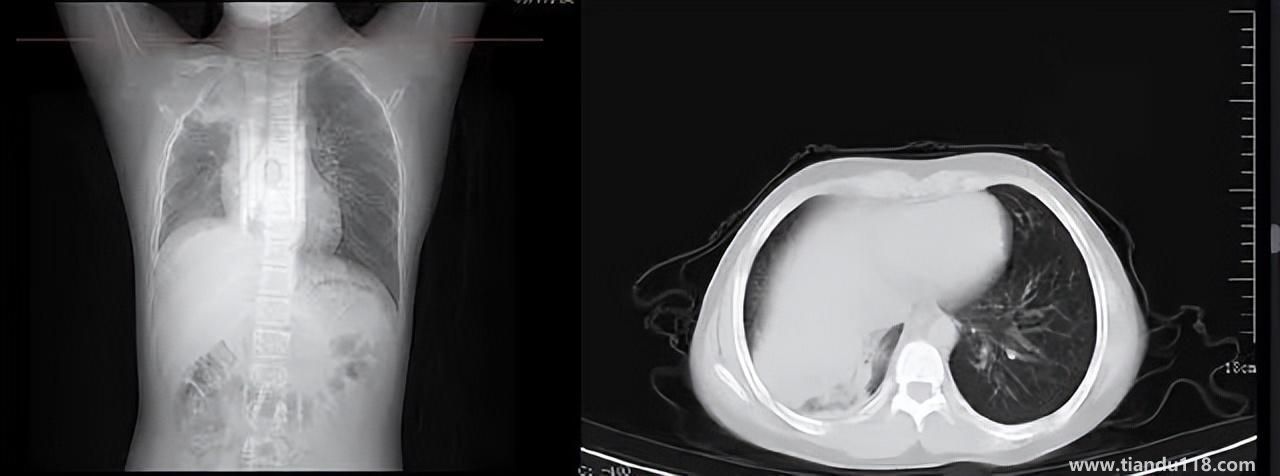

3個辦法可提前預(yù)警白肺(咋預(yù)防“白肺”) 3個辦法可提前預(yù)警白肺(咋預(yù)防“白肺”)家里有老人,擔(dān)心出現(xiàn)“大白肺”、“沉默型缺氧”等情況,具體如何應(yīng)對,提前預(yù)警?近日,大象新聞接到諸多咨詢。針對這些問題,大象新聞記者做了多方采訪。什么是白肺?對... 小編 2022-12-28 693

男孩咳嗽發(fā)熱在家硬扛成白肺(醫(yī)生表示以下幾種情況別硬“扛”) 男孩咳嗽發(fā)熱在家硬扛成白肺(醫(yī)生表示以下幾種情況別硬“扛”) 近日,一名12歲男孩咳嗽一周不就醫(yī),一側(cè)肺部“扛”成了“白肺”?!氨е鴥e幸心理一直在家硬‘扛’,沒想到‘扛’出這么重的?。 焙⒆蛹议L悔不... 小編 2022-12-28 939

為何有人出現(xiàn)“白肺”?專家回應(yīng)和疫苗接種無關(guān) 為何有人出現(xiàn)“白肺”?專家回應(yīng)和疫苗接種無關(guān)國務(wù)院聯(lián)防聯(lián)控機(jī)制12月27日召開新聞發(fā)布會,針對有媒體提問稱,從近期公眾的反映情況看,有的新冠病毒感染者在就診過程中發(fā)現(xiàn)了肺炎或者是CT出現(xiàn)了“白肺”的現(xiàn)... 小編 2022-12-27 817

感染新冠會變白肺?醫(yī)生:有年輕病例 感染新冠會變白肺?醫(yī)生:有年輕病例感染新冠會變白肺嗎?對此,有專家表示,造成“白肺”情況有很多種,感染新冠只是一種可能。少量患者肺有滲液 ,咳嗽不會引發(fā)白肺,有年輕人病例。... 小編 2022-12-27 608